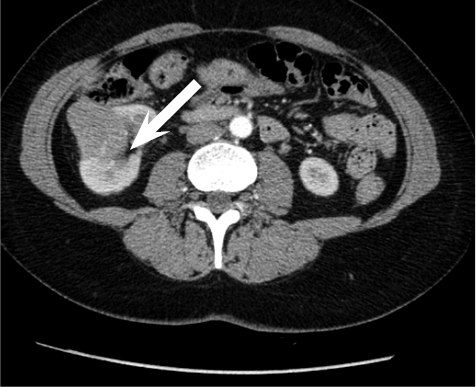

Pseudoaneurysm was embolized with two 8 mm x 20 cm coils, an additional coil of 12 mm x 30 cm (Figure 5).

Control angiography with contrast was performed. Pseudoaneurysm was completely occluded and no longer visible (Figure 6). No extravasation was found.

After embolization, creatinine decreased till 83 µmoL/L and eGFR was 73 mL/min/1.73 m2. Pseudo­aneurysm was no longer visible, as well as small segmental branches. Vascularization of renal parenchyma is reduced.

Contrast enhanced computed tomography was performed on patient as a check-up after pseudoaneurysm embolization. Scarring tissues near the lower lobe of resected right kidney and ~3 milimetres size hyperdensive lesion were found. Renal collectoric systems were not spread out. No signs of recidyves/progression of renal cell carcinoma were found.